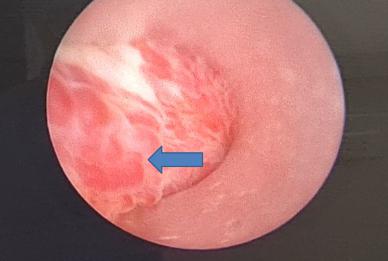

Sau khi làm một số xét nghiệm chuyên sâu, cộng với chụp công hưởng từ, bác sĩ nam khoa đã loại trừ được các nguyên nhân ác tính hay nhiễm khuẩn; và qua nội soi niệu đạo ngược dòng để chẩn đoán. Các bác sĩ đã phát hiện nguyên nhân gây chảy máu là do có nhiều mạch máu nông ở bề mặt niệu đạo giãn mỏng thành từng đám và rất dễ chảy máu.

Bệnh nhân được chẩn đoán là giãn vỡ mạch máu niệu đạo/ theo dõi u máu niệu đạo. Sau đó được chỉ định phẫu thuật nội soi đốt các mạch máu giãn bằng laser holmium.